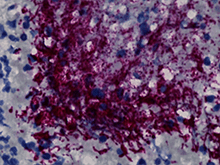

Gum Disease-Related Bacteria Tied to Colorectal Cancer

Fusobacterium nucleatum bacteria (purple) in a human colorectal cancer tumor.Fred Hutchinson Cancer Center

Scientists identified a specific subtype of Fusobacterium nucleatum — a type of bacteria implicated in gum disease — that may promote the growth of colorectal tumors. The study, which was partly funded by NIDCR, suggests that therapies targeting these bacteria in tumors could help reduce the severity of some colorectal cancers.